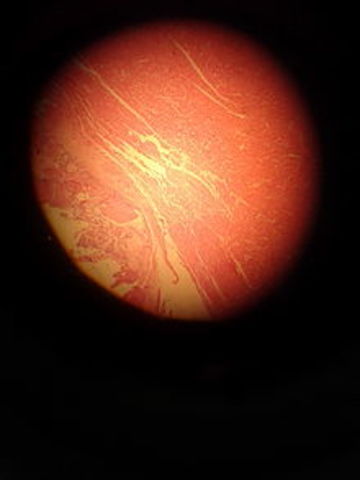

Histologia

• OSIFICACION

• CLASIFICACION DE LA HISTOLOGIA

CLASIFICACION DE LA HISTOLOGIA

Desde el punto de vista de la Biología general de los organismos, la existencia de tejidos (como nivel de organización biológico) solo se reconoce sin discusión en dos grupos de organismos, a saber; las plantas vasculares (parte del reino Plantae) y los metazoos (parte del reino animal). Ésta es la razón por la que se puede afirmar, que existen dos disciplinas separadas, a las que se llama histología animal e histología vegetal, cada una con contenidos y técnicas diferenciados.